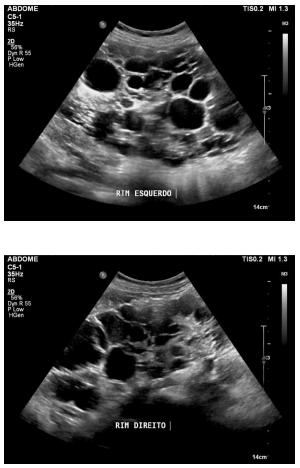

Paciente de 40 anos de idade, que não necessita de hemodiálise, apresenta as alterações identificadas nas imagens precedentes.

Com base nesse quadro clínico, julgue o item seguinte.

Os pacientes acometidos pela doença em questão apresentam maior risco de carcinoma de células renais, mesmo que não tenham a necessidade de realizar diálise.

Pacientes que apresentam as alterações mostradas nessas imagens raramente evoluem para quadros de insuficiência renal com necessidade de diálise, sendo essa doença responsável por menos de 1% dos pacientes dialíticos.

Os achados são típicos da doença renal policística autossômica recessiva.

As imagens mostram múltiplos cistos renais bilateralmente e, portanto, o paciente não demanda acompanhamento específico, pois as alterações observadas são benignas e sem significado clínico.

Anomalias associadas à doença em tela incluem aneurismas cerebrais, aneurismas da aorta abdominal e divertículos nos cólons.